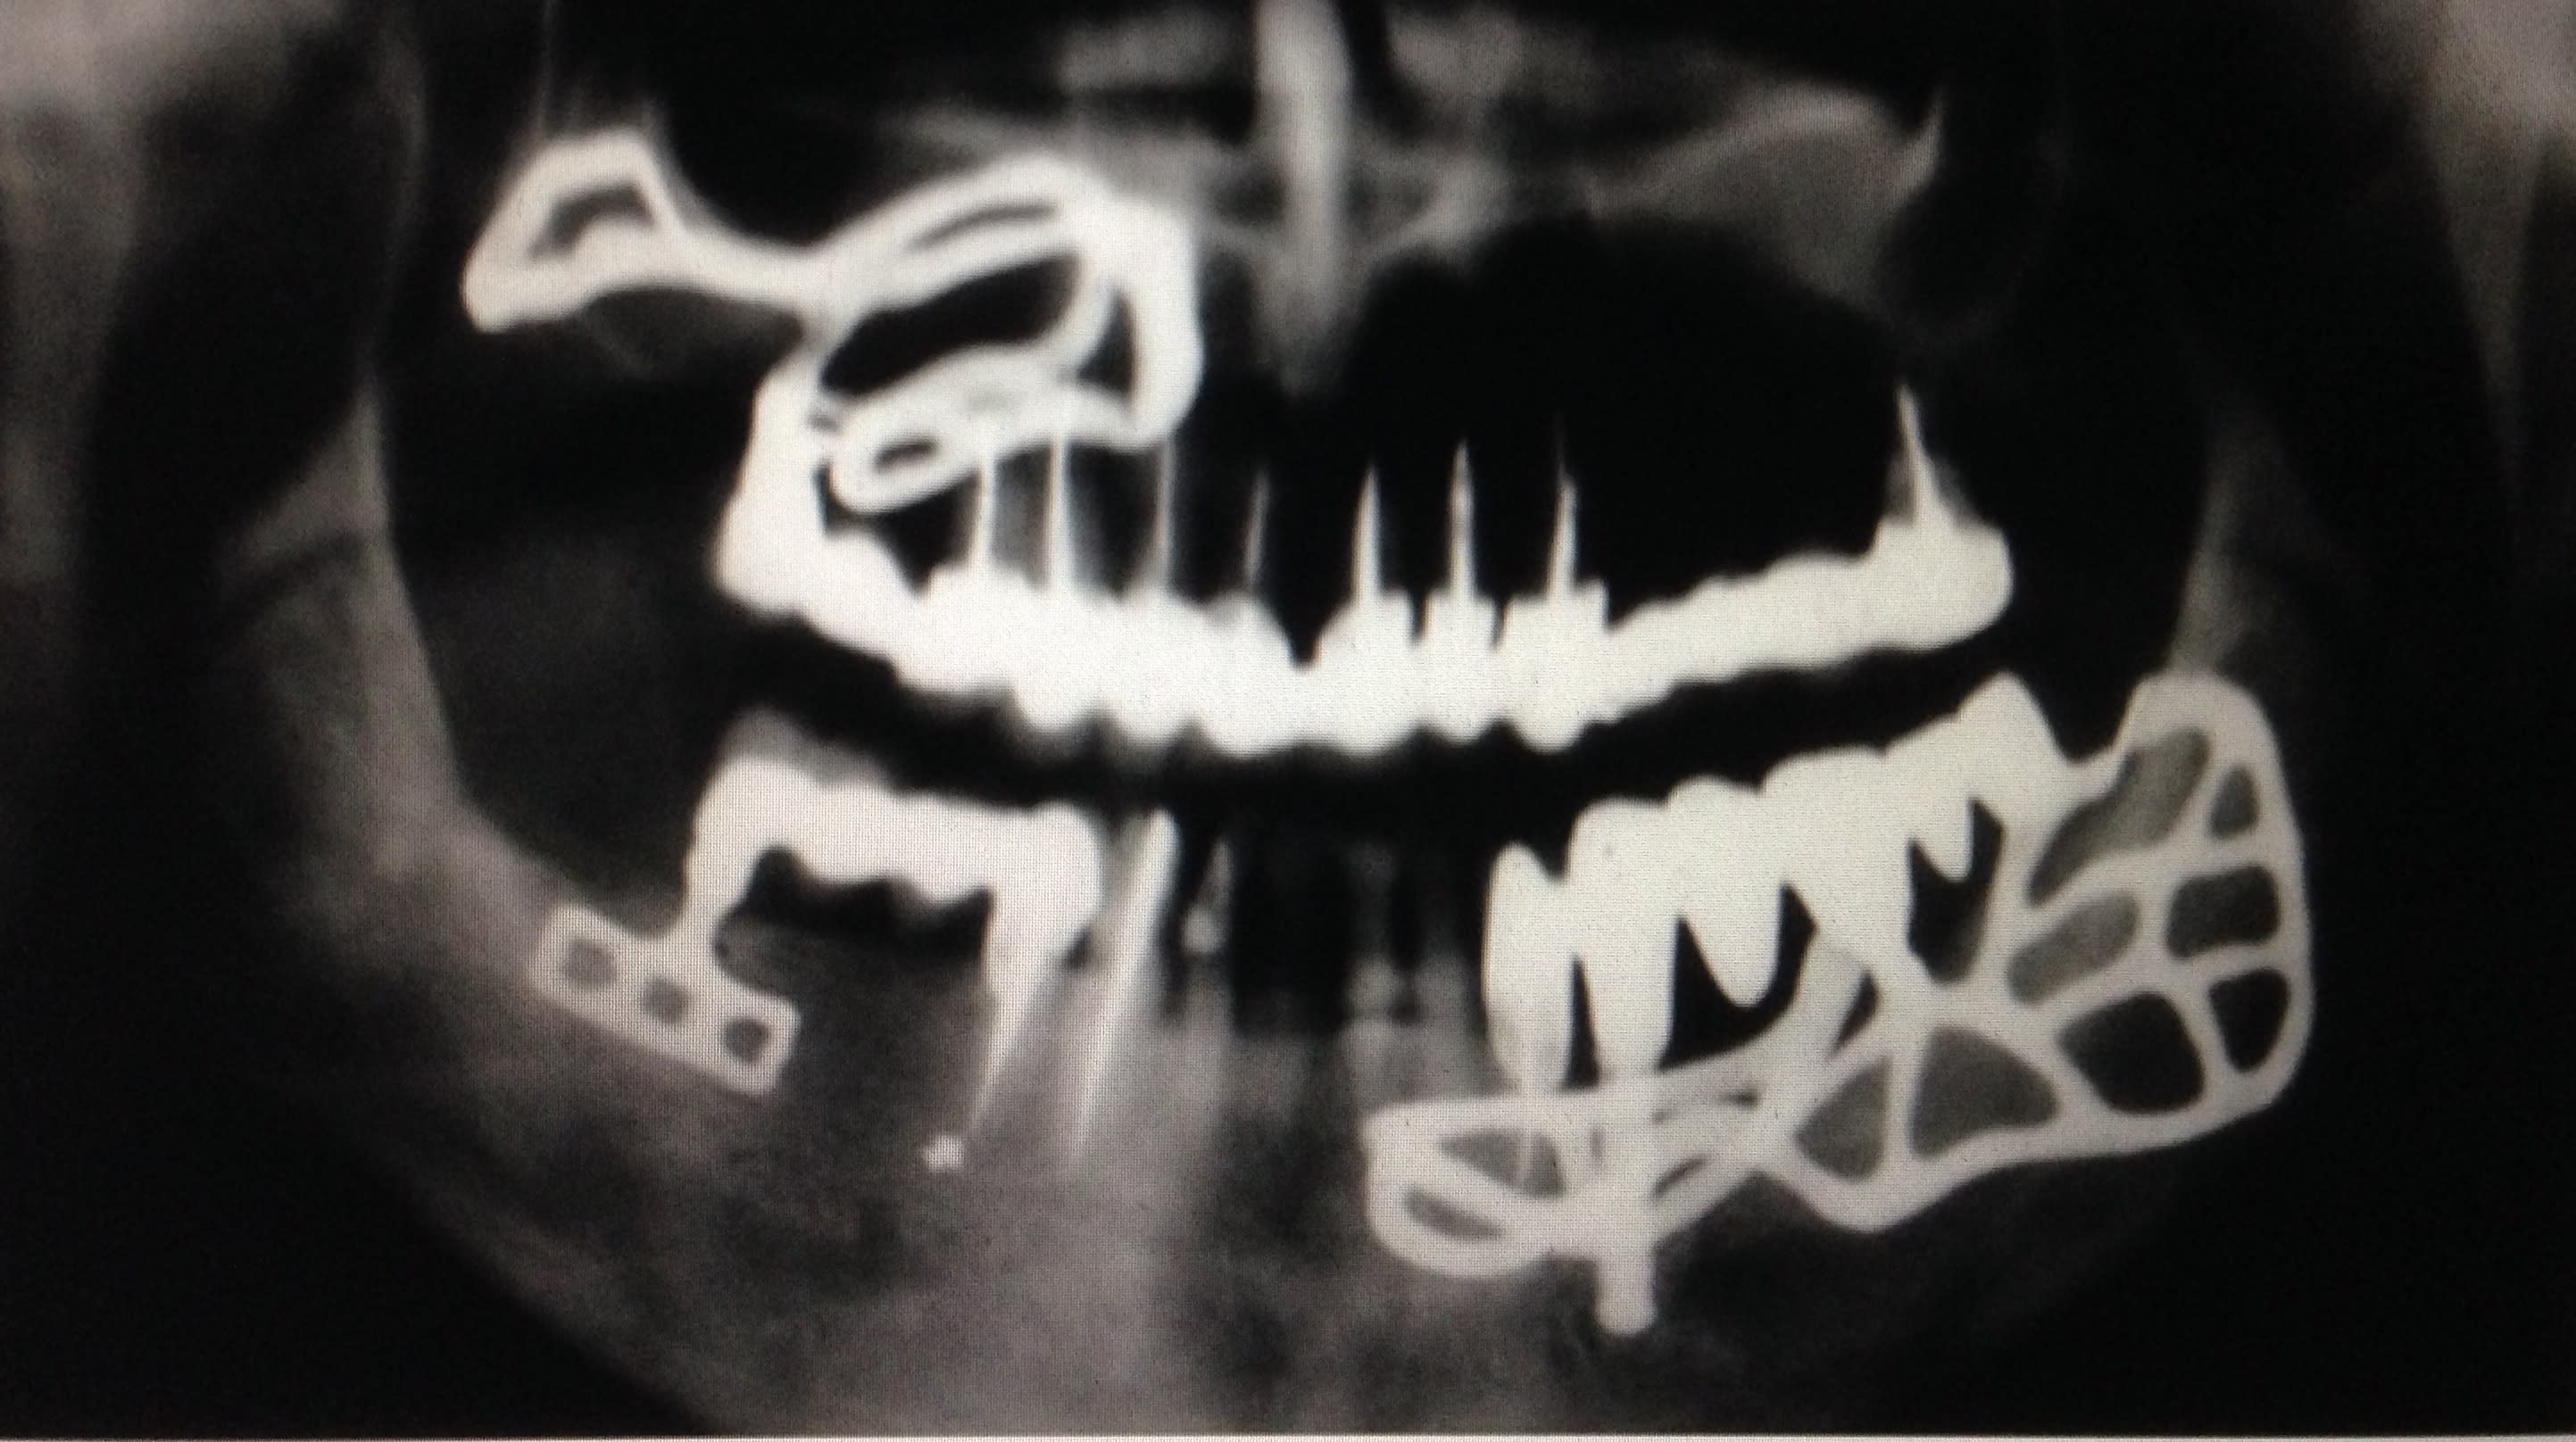

1949 Implant de golberg Et gershkoff sous periosté

Et là En photo c'est Linkow qui a repris l'idée et qui a fait du sous periosté aussi

J'ai commencé par ça, du sous périosté, palais décollé à 8 heures le prothésiste venait sur place, repartait avec l'empreinte, et pose le soir ou le lendemain matin....une autre époque....